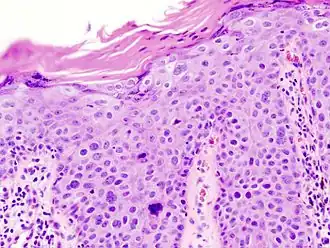

In situ disease

Bowen's disease is essentially equivalent to and used interchangeably with cSCC in situ, when not having invaded through the basement membrane.[12] Depending on source, it is classified as precancerous[13] or cSCC in situ (technically cancerous but non-invasive).[48][49] In cSCC in situ (Bowen's disease), atypical squamous cells proliferate through the whole thickness of the epidermis.[12] The entire tumor is confined to the epidermis and does not invade into the dermis.[12] The cells are often highly atypical under the microscope, and may look more unusual than the cells of some invasive squamous-cell carcinomas.[12]

cSCC in situ, high magnification, demonstrating an intact basement membrane.[12] -